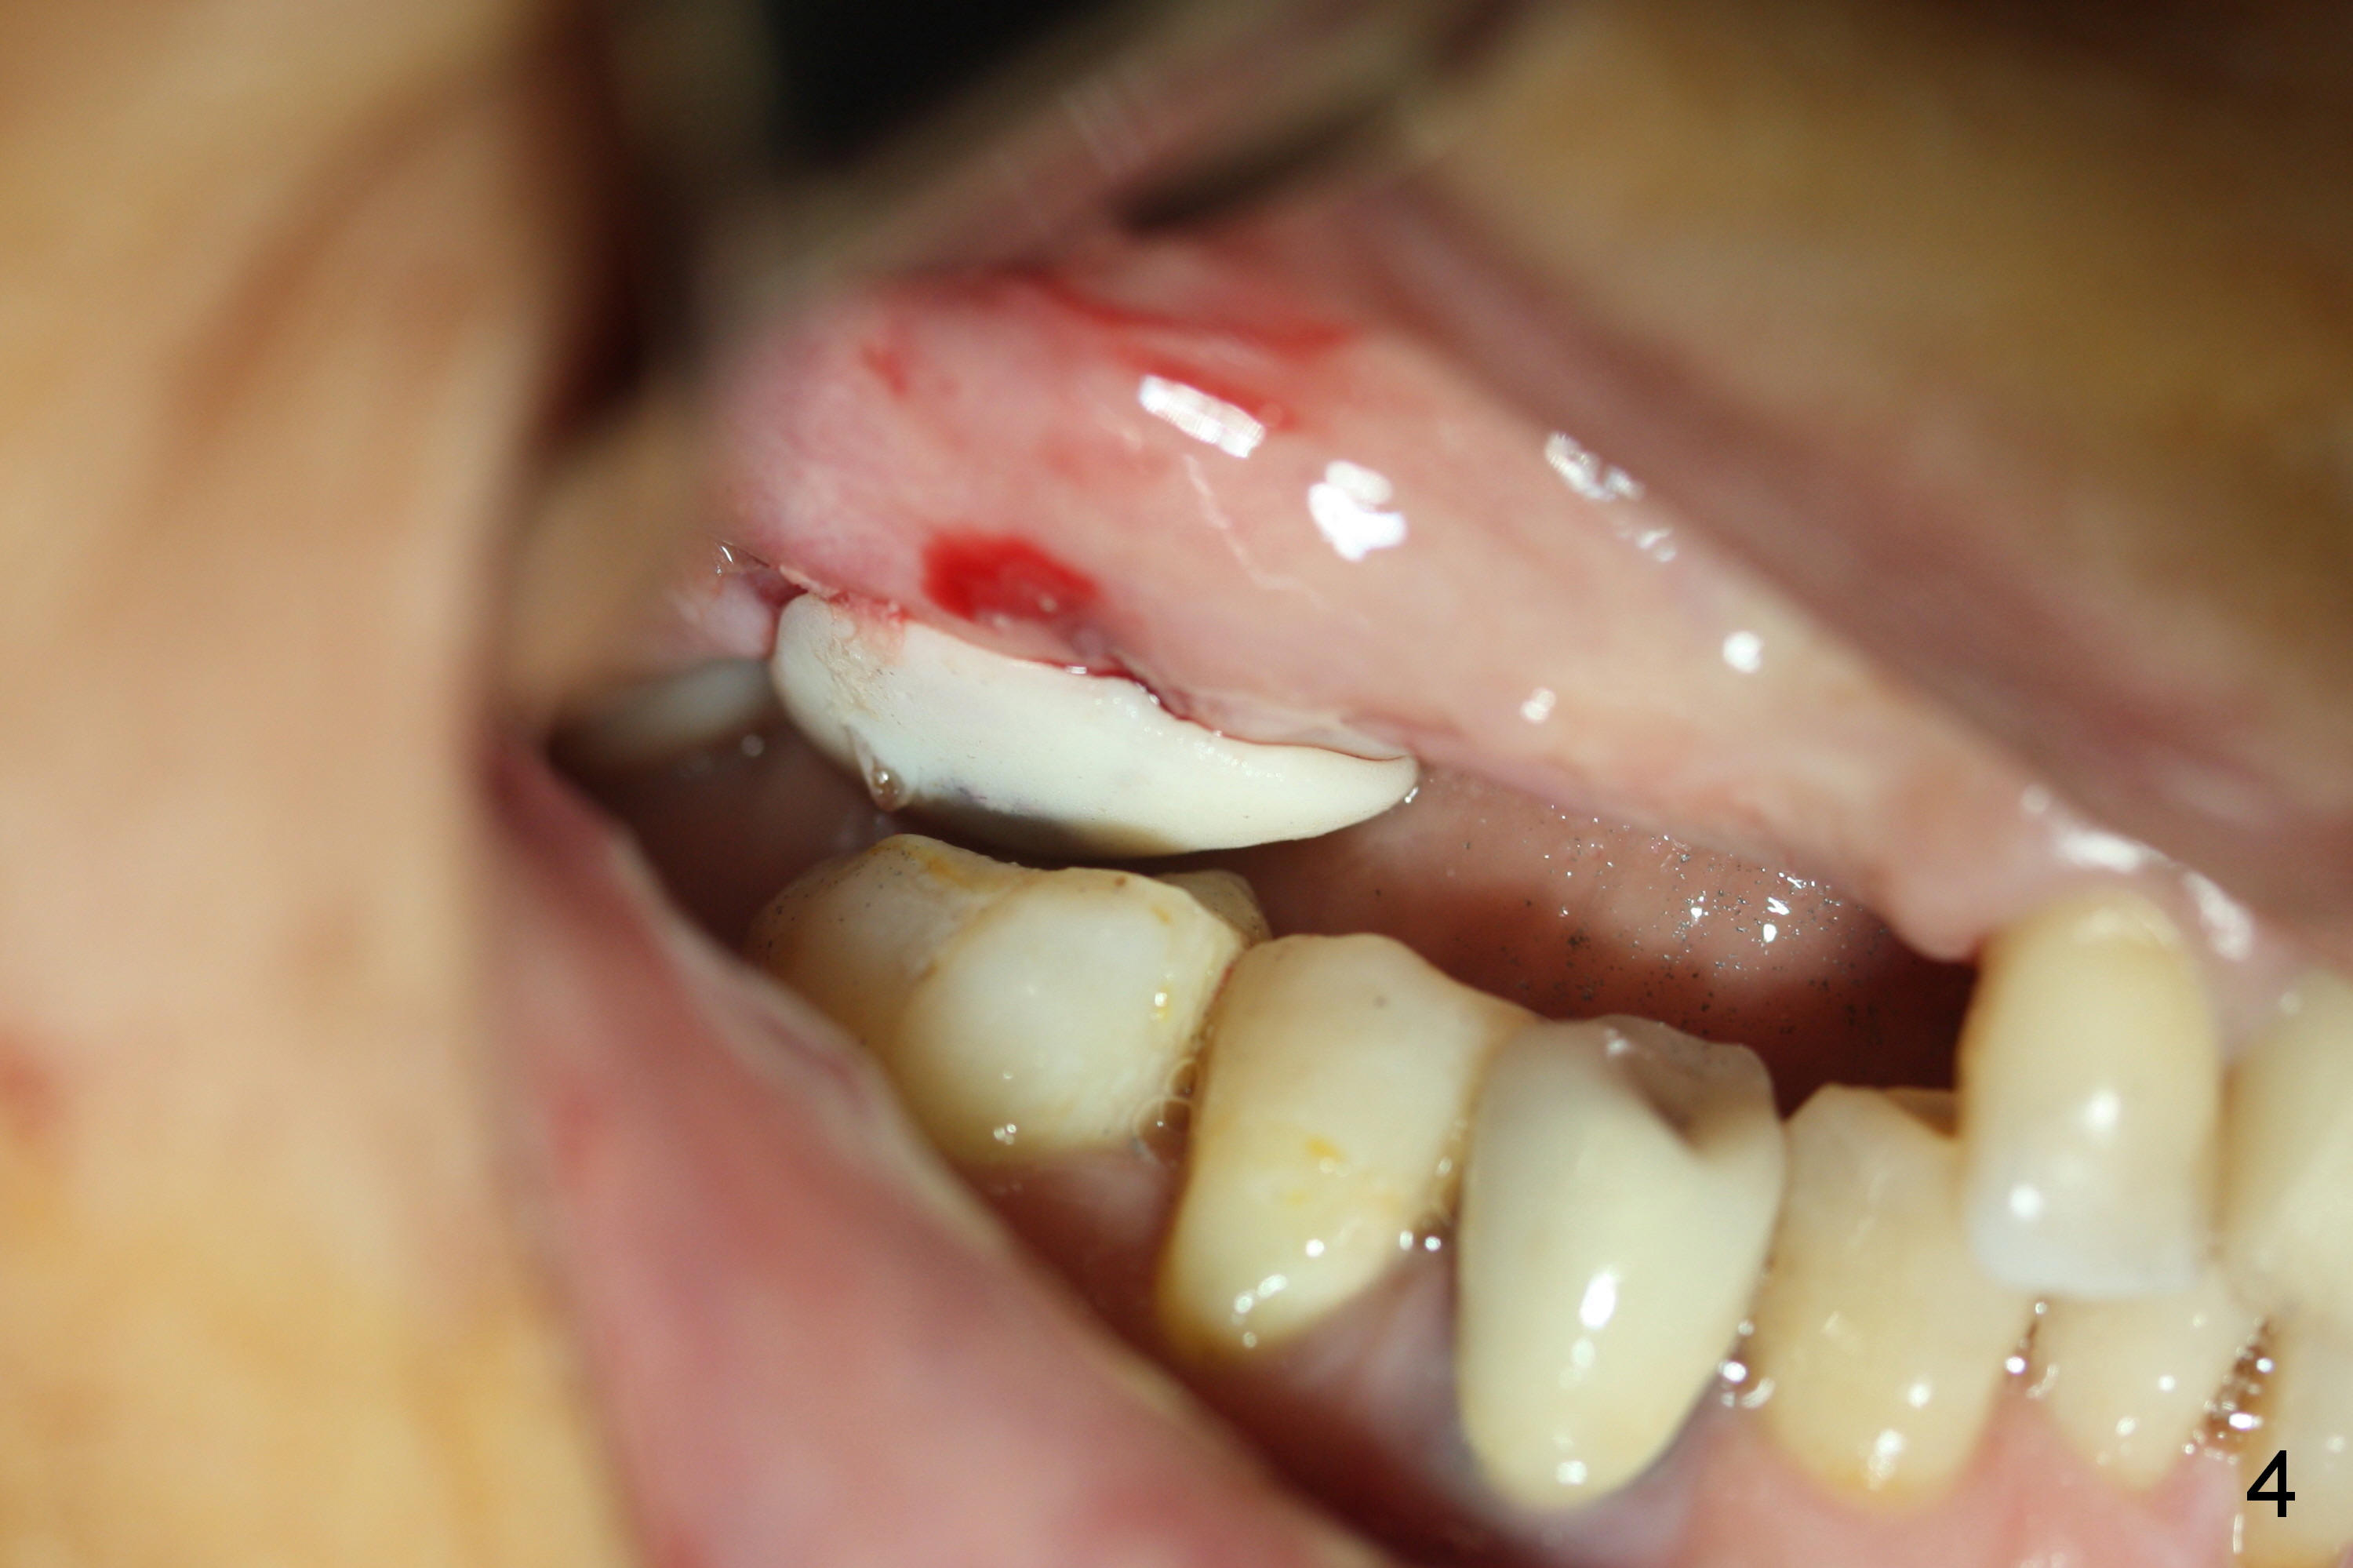

As planned, the osteotomy at #3 is underprep (using 3 mm reamer), followed by taps until 5x11 mm (Fig.1). When a 6x11 mm implant is being placed with high torque (Fig.2 (*: sinus lift)), bone mesiobuccal to the implant is starting to green-stick fracture. After flap suturing, a 5x3 mm abutment is placed and adjusted for the height. In fact the long vertical edentulous space is an artifact. An immediate provisional is fabricated with clearance (Fig.3,4). The adaptation of the provisional to the implant/abutment is so good that cement is not necessary for retention. When the wound heals, the provisional is too short to be retentive. It is not recemented. A healing screw is placed until the implant is restored.